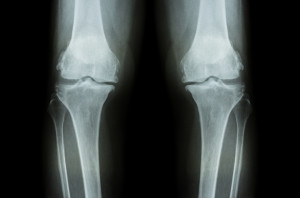

筋肉の秘密(変形性膝関節症)

変形性膝関節は厚労省調べで約1000万人程度いるそうです。この変形性膝関節は初期では立ち上がり、歩きはじめなど動作の開始時のみに痛み、歩き出すと痛みが軽減していきます正座や階段の昇降が困難となり、末期になると安静時にも痛みがとれず、水がたまり、変形がめだち、膝が伸びなくなり歩行が困難となります。

変形性膝関節症の多くの方は膝が伸びません。

膝が伸びない状態が続くと徐々に膝関節周囲の靭帯が緩んだり損傷する事でO脚やX脚になっていきます。